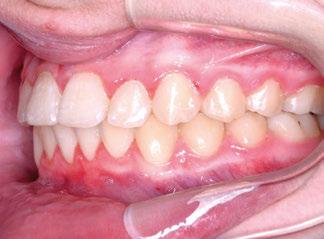

La niña de las figuras 1 a 3 presenta una leve asimetría facial con patrón braquifacial por tercio inferior disminuido y mentón desviado ligeramente hacia la derecha; los labios son competentes y en sonrisa apenas se exponen los incisivos. El perfil es excesivamente convexo,

con escasa proyección del mentón, y con los ángulos de la convexidad (155 º) y mentolabial (70 º) disminuidos y el nasolabial (103 º) en norma.

La exploración intraoral (figuras 4 a 8) revela una Clase II molar y canina completa, líneas 1/2 dentarias superior 0,5 mm e inferior 1 mm ambas desviadas hacia la derecha, los incisivos superiores excesivamente protruidos y vestibulizados (seguramente debido a la interposición del labio inferior), resalte de 13 mm y sobremordida 2/3 de corona. La discrepancia oseodentaria

inferior es de -3,5 mm y la curva de Spee de 4 mm.